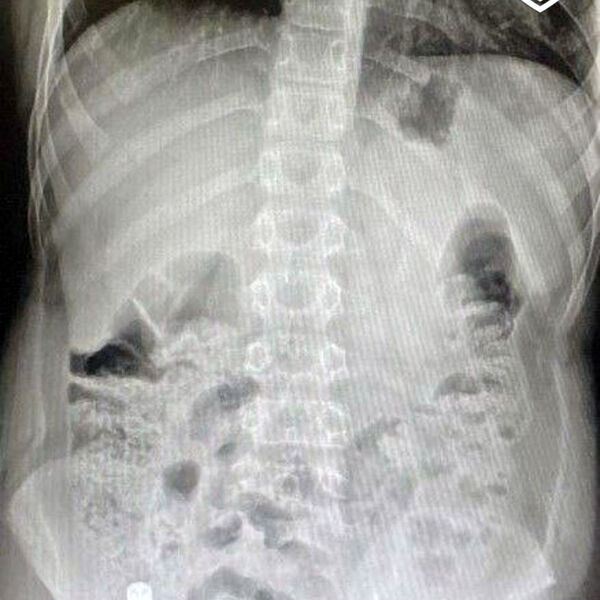

В медучреждение 12-летнего пациента привезли родители. Они рассказали, что сын проглотил батарейку из пульта от телевизора. Между моментом инцидента и обращением за помощью прошло очень мало времени. За это время инородное тело успело опуститься в слепую кишку. Врачи приняли решение о немедленном извлечении предмета.

«Вначале выполнили лапароскопию, чтобы визуализировать как возможные осложнения, так и расположение инородного предмета. Затем провели эндоскопическое исследование, во время которого с помощью специальной петли извлекли литиевую батарейку», — поделился детский хирург, заведующий хирургическим отделением №1 Игорь Хворостов.